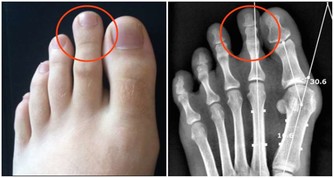

- 降低腫瘤生長:綠茶中的兒茶素可抑制癌細胞增殖,特別是在乳腺癌、前列腺癌、結腸癌方面,有一定保護作用。